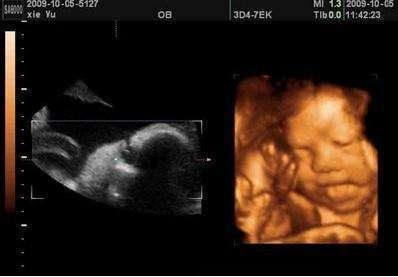

在血管检查中,EDV指的就是血管内腔容积,能反映血管的充盈程度。通过测量PSV(收缩期最大流速)和EDV(舒张末期血流速度),医生能轻松判断血管是否狭窄或硬化。心脏检查时,EDV正常值男女略有差异:男性约125ml,女性约110ml。搭配ESV(收缩期容积)、SV(每搏输出量)等指标,简直成了心脏健康的"体检套餐"! -